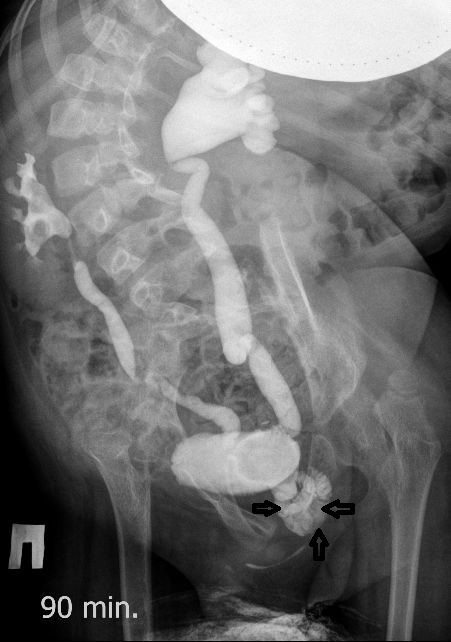

Всё верно, только что вот это ?

И что законтрастировалось на экскреторных урограммах около мочевого пузыря?

DX0004.jpg

Стриктура уретры с расширением ее проксимального отдела?

Если честно, и я изначально не совсем понял, где находится конкремент (а это конечно же конкремент), локализованный на урограммах. При первичном исследовании на УЗИ его я не видел (либо он спрятался за тенью конкремента мочевого пузыря, либо я обрадовался редкой находке конкремента такого размера в мочевом пузыре - 2.5 см, и не посмотрел что ниже). Тем не менее при ретроспективном анализе архивированных сонограмм, как мне кажется, он попал в один из сканов, м.б. не совсем чётко.

И всё -же, где конкремент :?:

Возможно, в дивертикуле либо в нижней трети мочеточника..

Верификация:

Выдержка из протокола операции- "...вскрыт мочевой пузырь, обнаружен камень 4 х 3х 2.5 см, плотный, удалён. При дальнейшей ревизии мочевого пузыря обнаружен вколоченный камень в шейке мочевого пузыря и в уретре, удалён камень 2 х 1.5 х 1.5 см. При осмотре устья левого мочеточника - последний зияет, мочеточник расширен до 1 см, учитывая расширение мочеточника, проведена антирефлюксная пластика по Грегуару..."